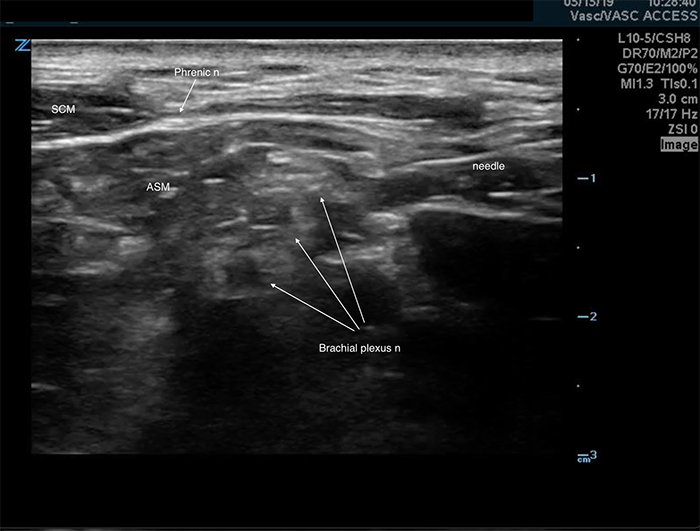

- The ipsilateral phrenic nerve overlies the anterior scalene muscle near the interscalene space. (Figure 4) It is affected during an interscalene nerve block,5 suspected to occur via anterior spread of the anesthetic. Although this complication is associated with a significant reduction in pulmonary function tests,5,6 it is well tolerated in most healthy patients.5,6 Care should be taken in patients with respiratory compromise or underlying lung disease.

Figure 4. Phrenic nerve

- In-plane approach from the posterior side of the probe is preferred.

- Insert the block needle 5 mm at ~30 degrees to the skin surface at the posterior side of the probe.

- Identify the needle tip and ensure it is always in view.

- Advance the needle toward the plexus.

- Pass through the prevertebral fascia, which is a dense, echogenic layer overlying the scalene muscles that resists needle penetration. It may produce a “click” felt in the needle when passed through.

- Slowly advance the needle towards the plexus.

- Goal is to inject between elements of the plexus.

- Care is taken not to violate the individual elements of the plexus.

- Common target is between the top and second trunk.

- Once movement of the needle causes movement on the plexus, injection may begin.